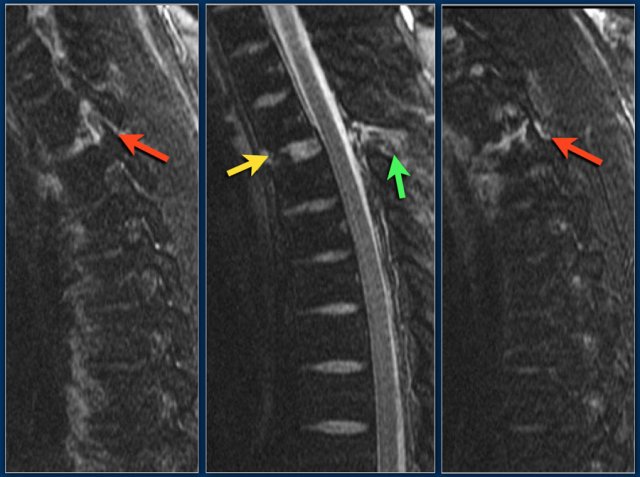

The images are of a patient with a typical bamboo spine as a result of ankylosing spondylitis.

After a fall on his back no fracture was seen on the x-rays.

However the CT shows a thin fracture line through the anterior side of the vertebral body and also through the spinous process.

Continue with the MR-images.

Look at the images.

What are the findings?

Then scroll to the next images.

The findings are:

1. Vertebral bodies show marrow edema as a result of a fracture.

2. Torn flaval ligament (yellow arrow).

3. Fractures through the posterior elements (red arrows).

The TLICS-score is high, because there is distraction and injury to the PLC.